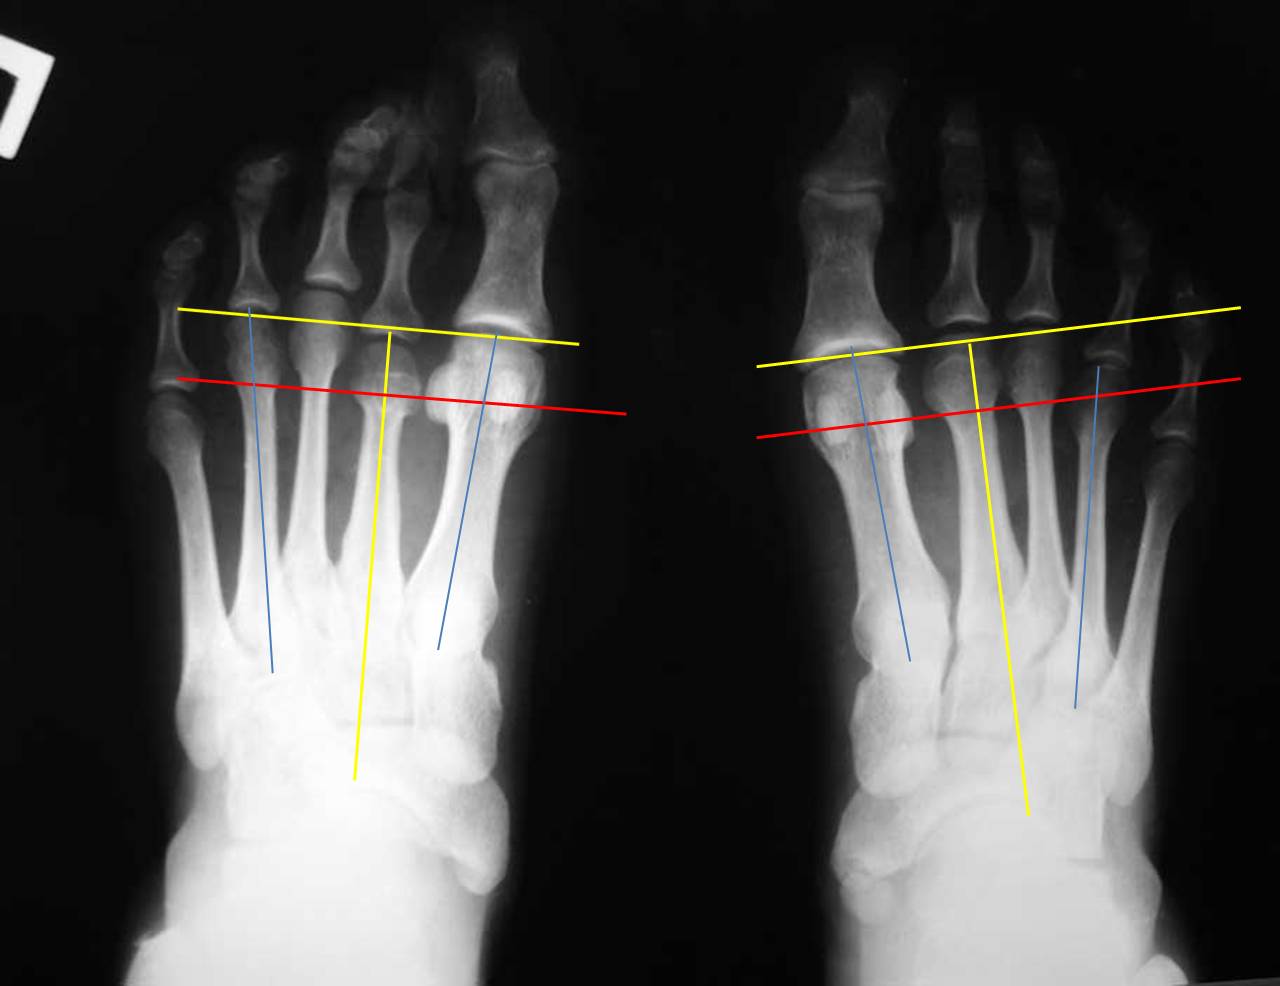

Я провел несколько ориентиров на представленных рентгенограммах, чтобы показать разницу в биомеханических ситуациях. На левой стопе перпендикуляр, проведенный к оси 2 плюсневой кости через дистальный конец 1 плюсневой (желтые линии) (принято за ориентир брать ось 2 плюсневой кости) проходит через верхушки 2 и 3 плюсневых. В нормальной ситуации 2 плюсневая кость должна быть чуть длинее 1-й. То есть на левой стопе можно говорить об относительно длинной 1 плюсневой кости. Именно этим объясняется наличие у молодой женщины признаков артроза 1 плюснефалангового сустава. А вот длина 4 плюсневой кости на левой стопе нормальная: перпендикуляр к оси 2 плюсневой проходит через середину латеральной сесамовидной кости и середину головки 4 плюсневой (красная линия). Теперь посмотрите на правую стопу: 3-я плюсневая кость намного длинее 1-й, а 4-я такой же длины. Такого в норме никак не может быть. А вот вторая при правильной разметке оказывается совсем чуть чуть короче первой. При этом абсолютная длина 1-й плюсневой (в милиметрах) у меня получилась на левой стопе даже больше, а длина 4 плюсневой на правой стопе на 4мм больше, чем на левой (голубые линии). Вот и получается, что на правой стопе наряду с небольшим укорочением 2 плюсневой есть более значимое относительное удлинение 3 и 4 плюсневых. И это в перспективе может быть причиной центральной метатарсалгии. Но пока жалобы пациентки связаны только с молоткообразной деформацией 2 пальца, лечение должно быть направлено на ее устранение наименее травматичным способом.